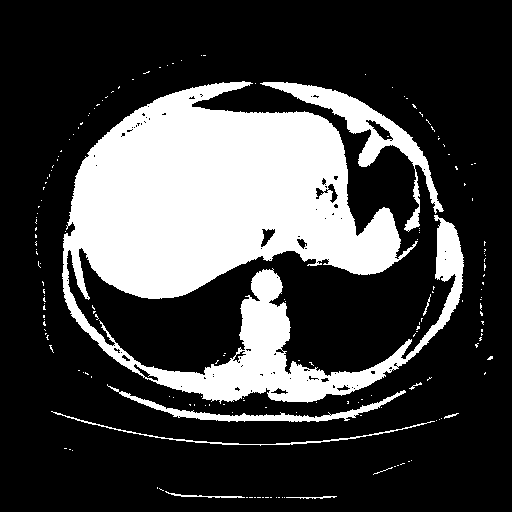

Generated VENOUS CT scan (A→B translation)

Full window (WL 1023.5, WW 4095 β†’ Low βˆ’1024, High +3071)

Actual HU range: [-1024.0, 3071.0]